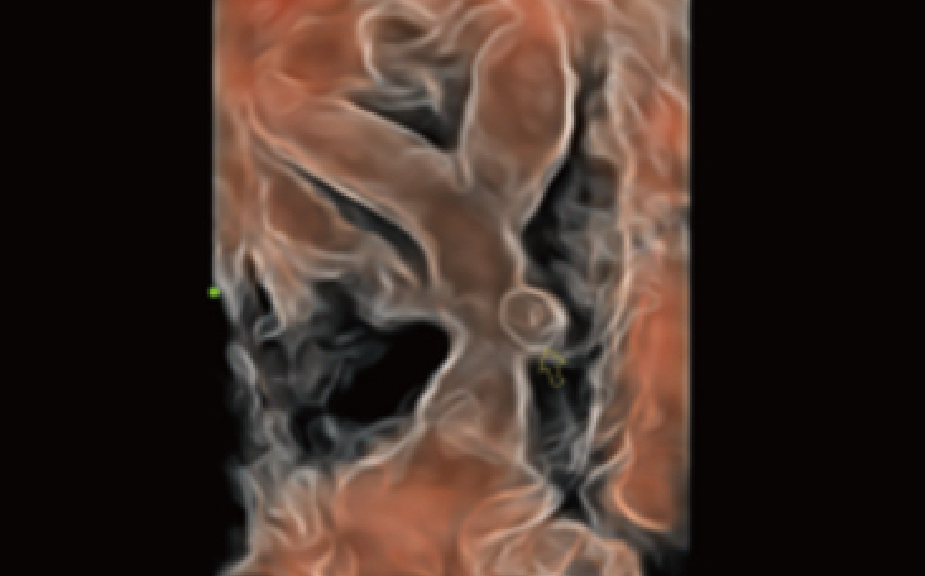

Antes del embarazo

Embarazo

Antes del embarazo

Embarazo